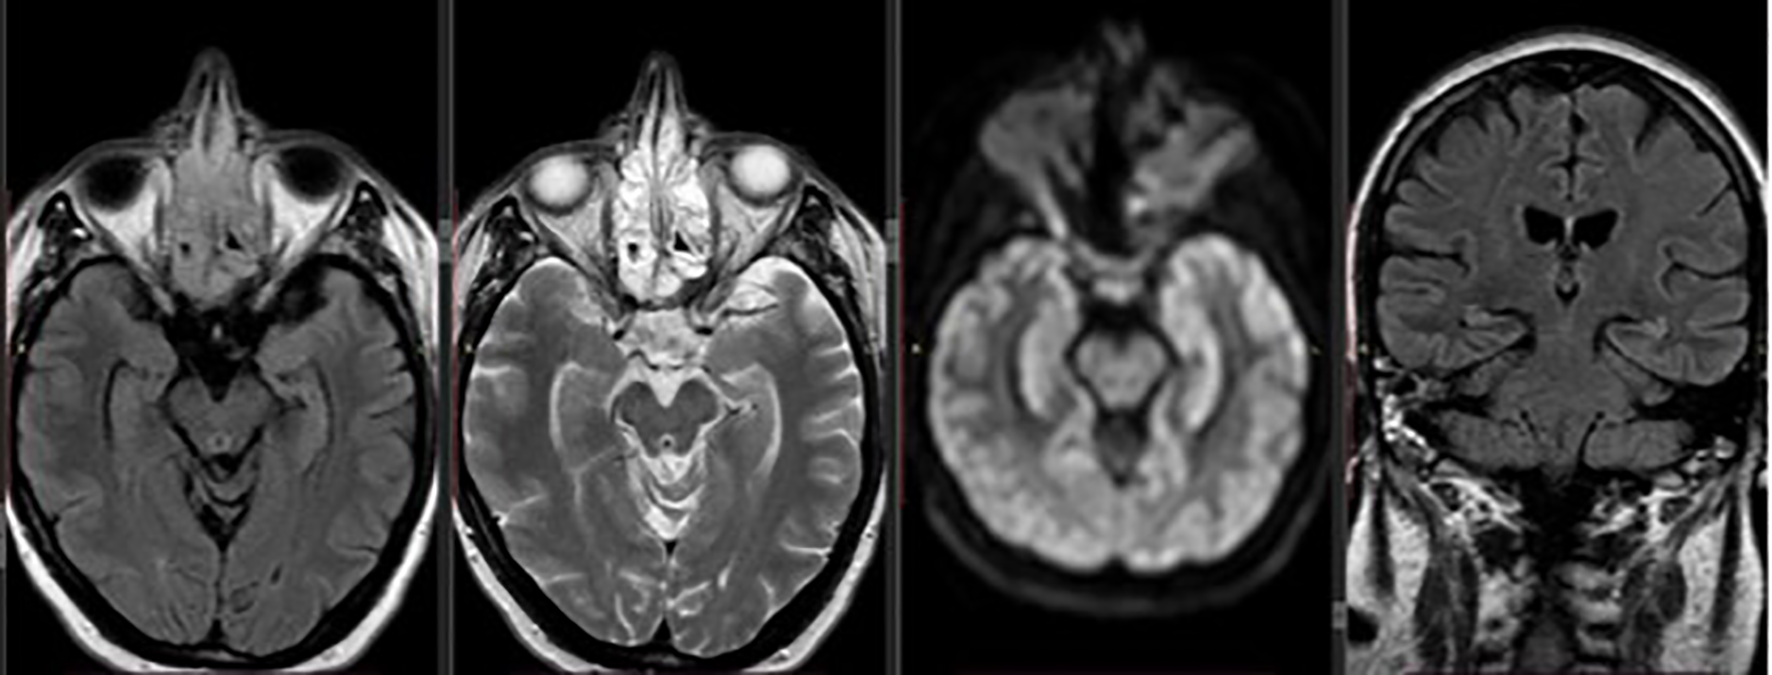

Five days after admission the patient remained stuporous, with further deterioration of her mental status and totally unable to perform any activity. Brain MRI was performed and T2 images revealed abnormal signal in the periaqueductal gray matter of the upper pons and midbrain area (Figure 1), findings that are typical for Wernicke’s encephalopathy.

Figure 1

Axial and coronal brain MRI demonstrating T2/FLAIR hyperintensity in the periaqueductal gray matter of the upper pons and midbrain, consistent with findings typically seen in Wernicke’s encephalopathy.